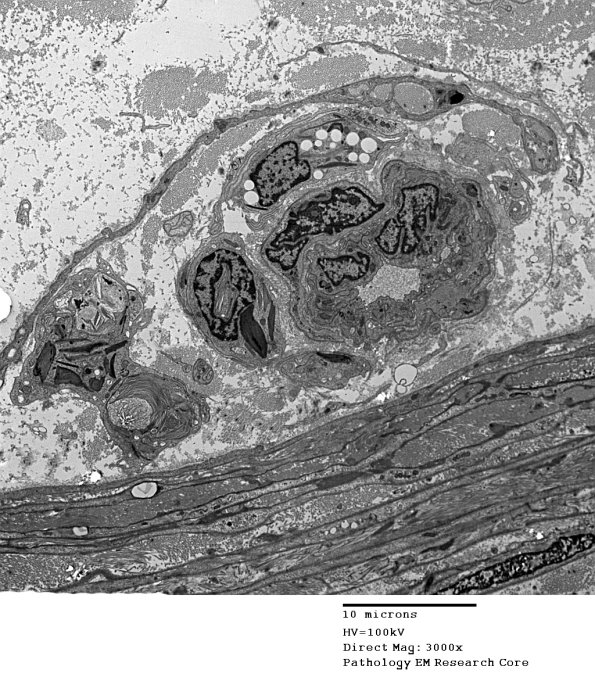

4J1,2 In this case the macrophage contains numerous Schwann cell derived pi granules.